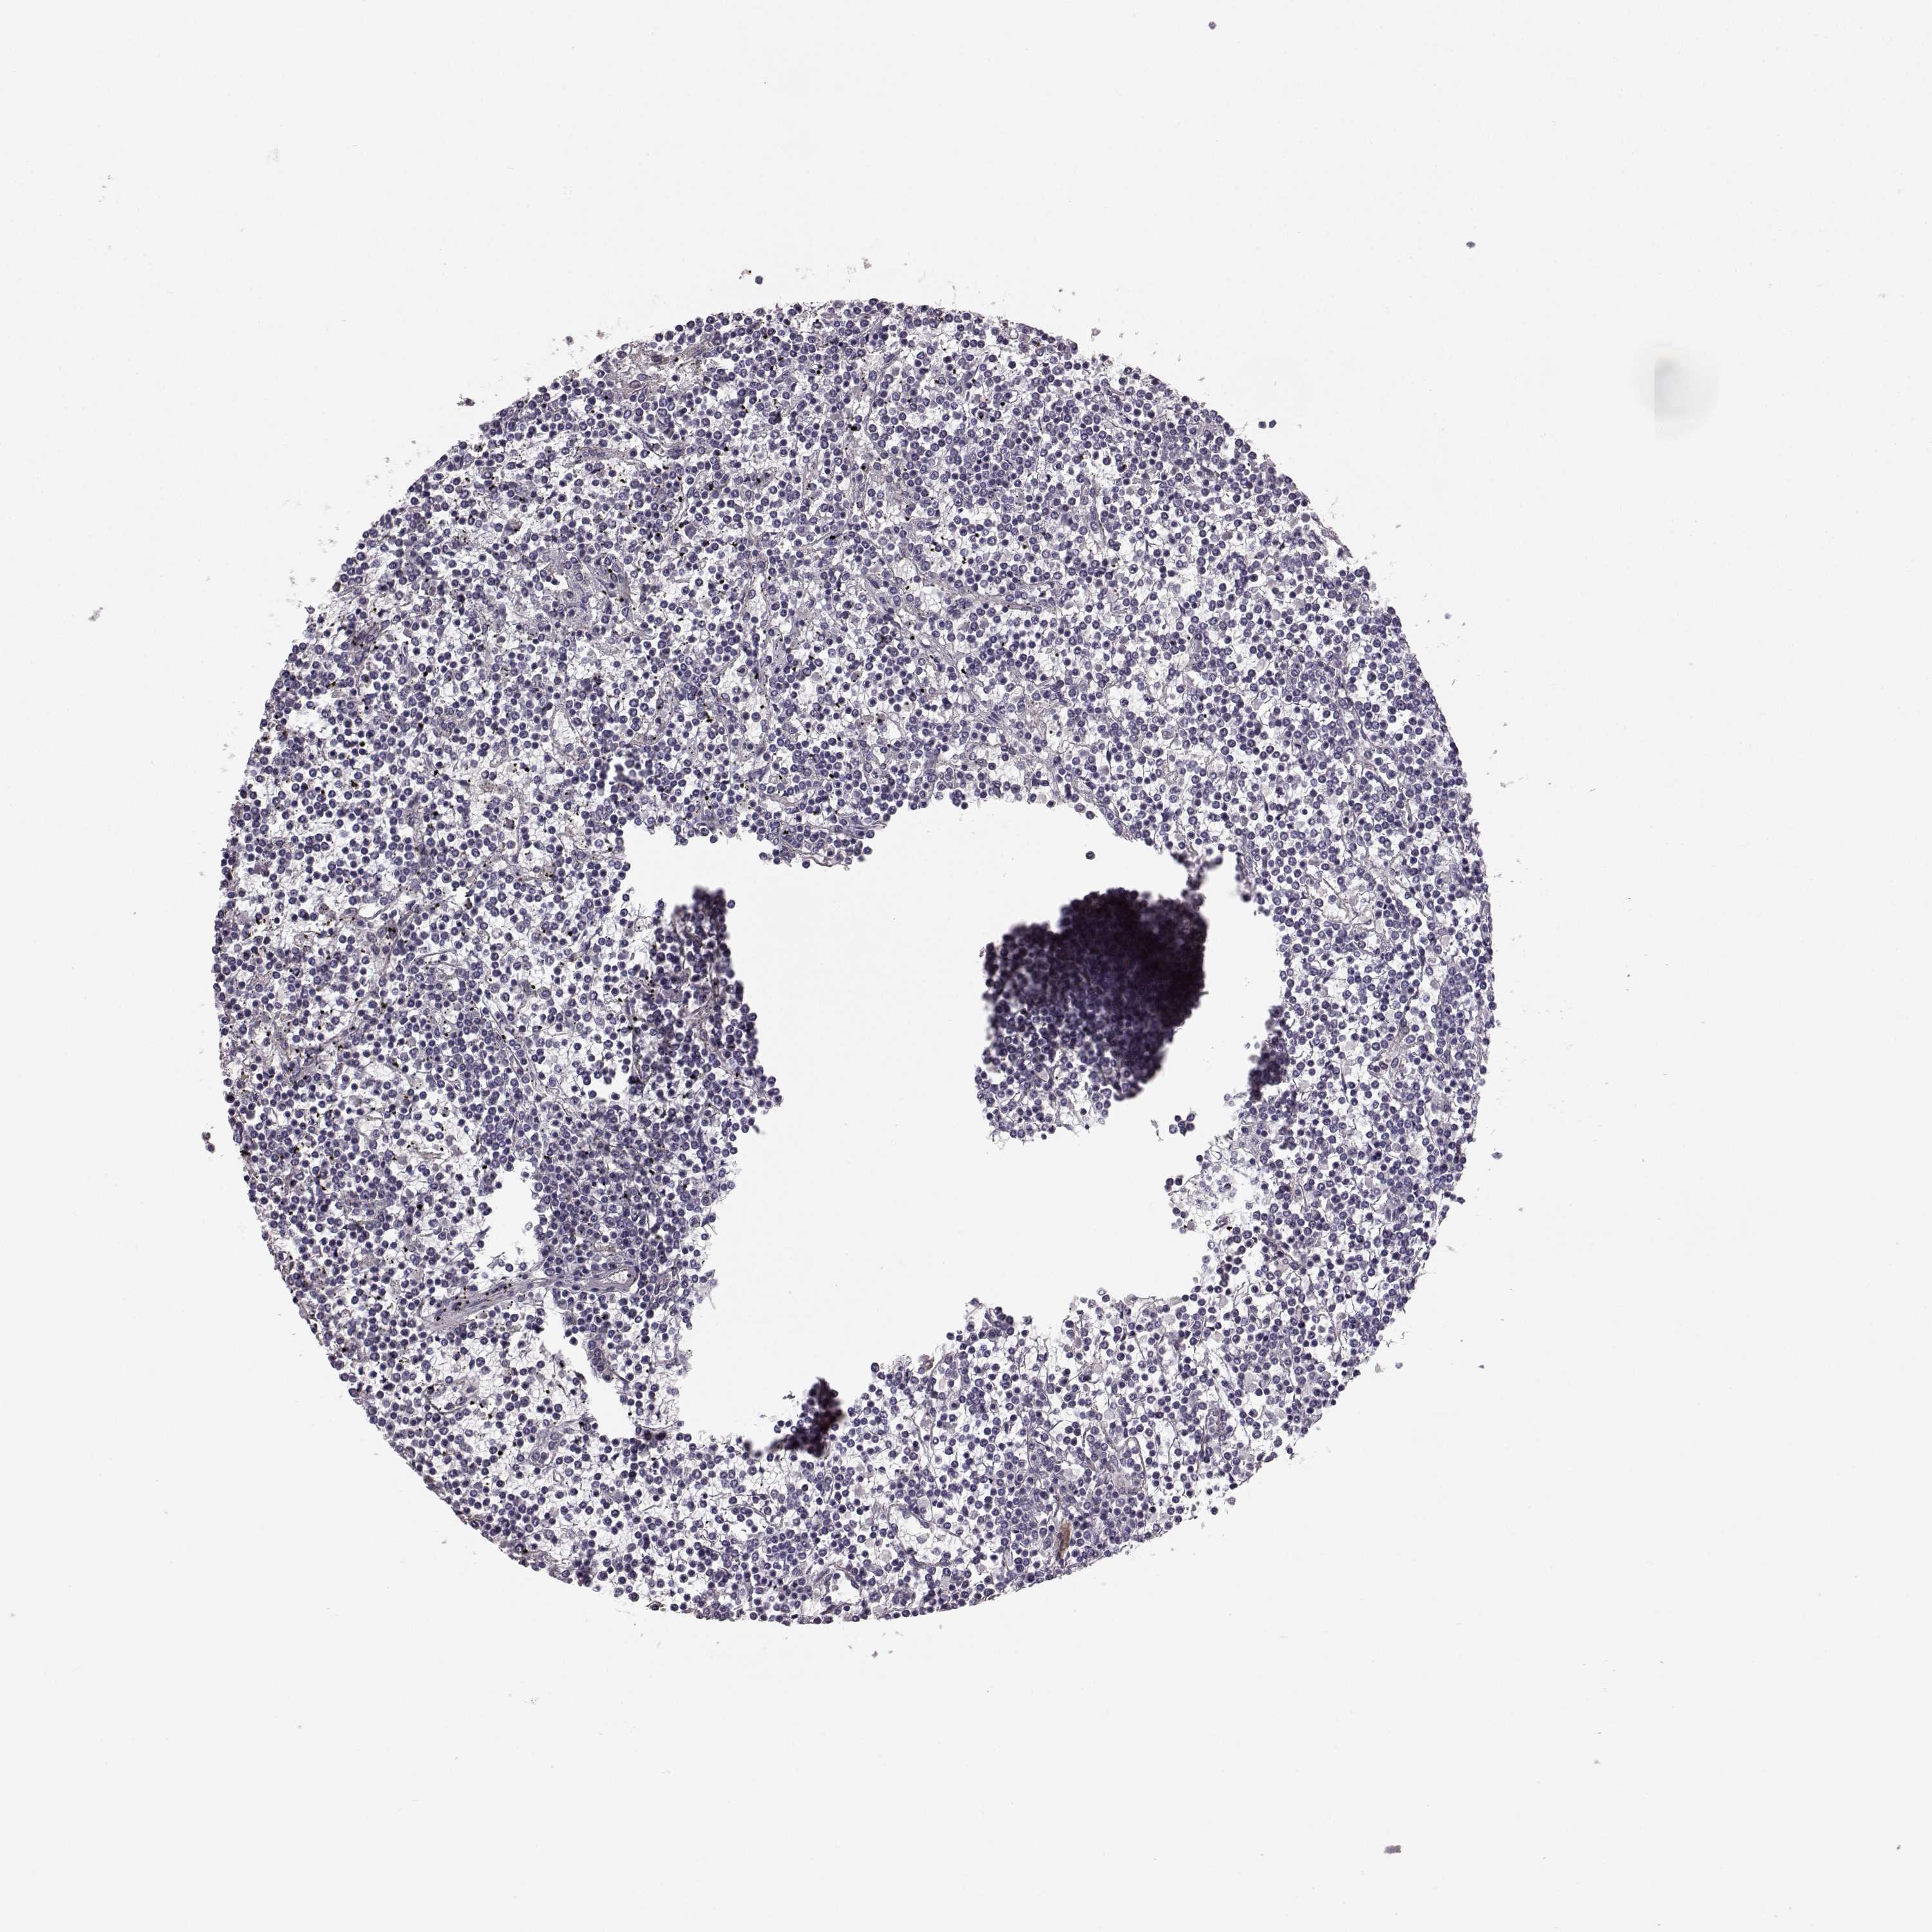

LYMPHOMA - Protein expressioni

A mouse-over function shows sample information and annotation data. Click on an image to view it in a full screen mode. Samples can be filtered based on level of antibody staining by selecting one or several of the following categories: high, medium, low and not detected. The assay and annotation is described here.

Each image is clickable and will lead to virtual microscopy that enables deeper exploration of all samples and also displays staining intensity scores, fraction scores and subcellular localization as well as patient and tissue information for each sample.

Antibody HPA045339

Staining

High

Intensity

Strong

Quantity

>75%

Location

Nuclear

Malignant lymphoma, non-Hodgkin's type, Low grade

Malignant lymphoma, non-Hodgkin's type, High grade

Hodgkin's disease, NOS